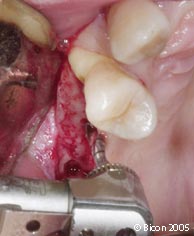

21. |

使用模板确定种植体位置的轨道。 |